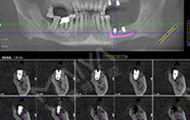

拍摄了CT,牙齿哪个地方有问题,看的很清楚,非常科学。但是口内有牙周病,需要先治疗再进行种牙,而且他们服务特别好,等待的时候还给倒水,安抚我让我感到很亲切,做了口内全口洁牙+喷砂+抛光+上药去除牙结石,是两个护士给洗的牙,一个细节就能提现这个机构好不好,卫生、环境方面都很不错,我也希望可以早点治疗好,做种植牙!